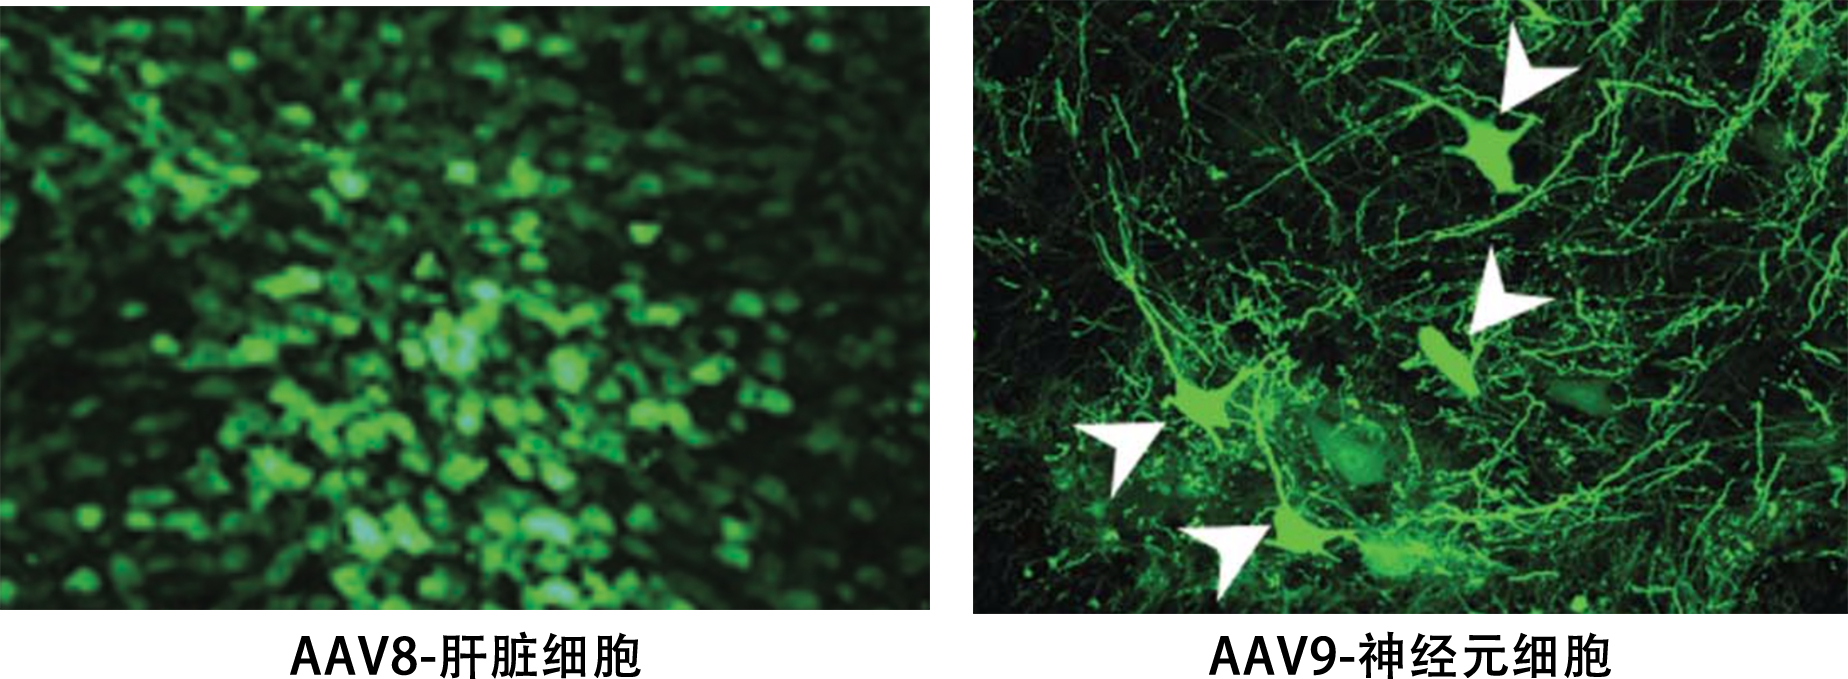

研究中采用的重组腺相关病毒载体(rAAV)是在非致病的野生型AAV基础上改造而成的基因载体。AAV具有多种血清型,不同血清型的AAV载体的主要区别是衣壳蛋白不同,不同的衣壳蛋白的蛋白结构结合的细胞外受体分子不一样,所以不同的血清型对组织或器官有着不同的靶向亲和性。由于宿主范围广、安全性高、免疫原性小、表达周期久等优点,已被广泛地应用于基础研究和临床试验中。

AAV8 |

神经系统 |

|

肝脏 |

AAV9 |

肺 |

心脏 |

肌肉 |